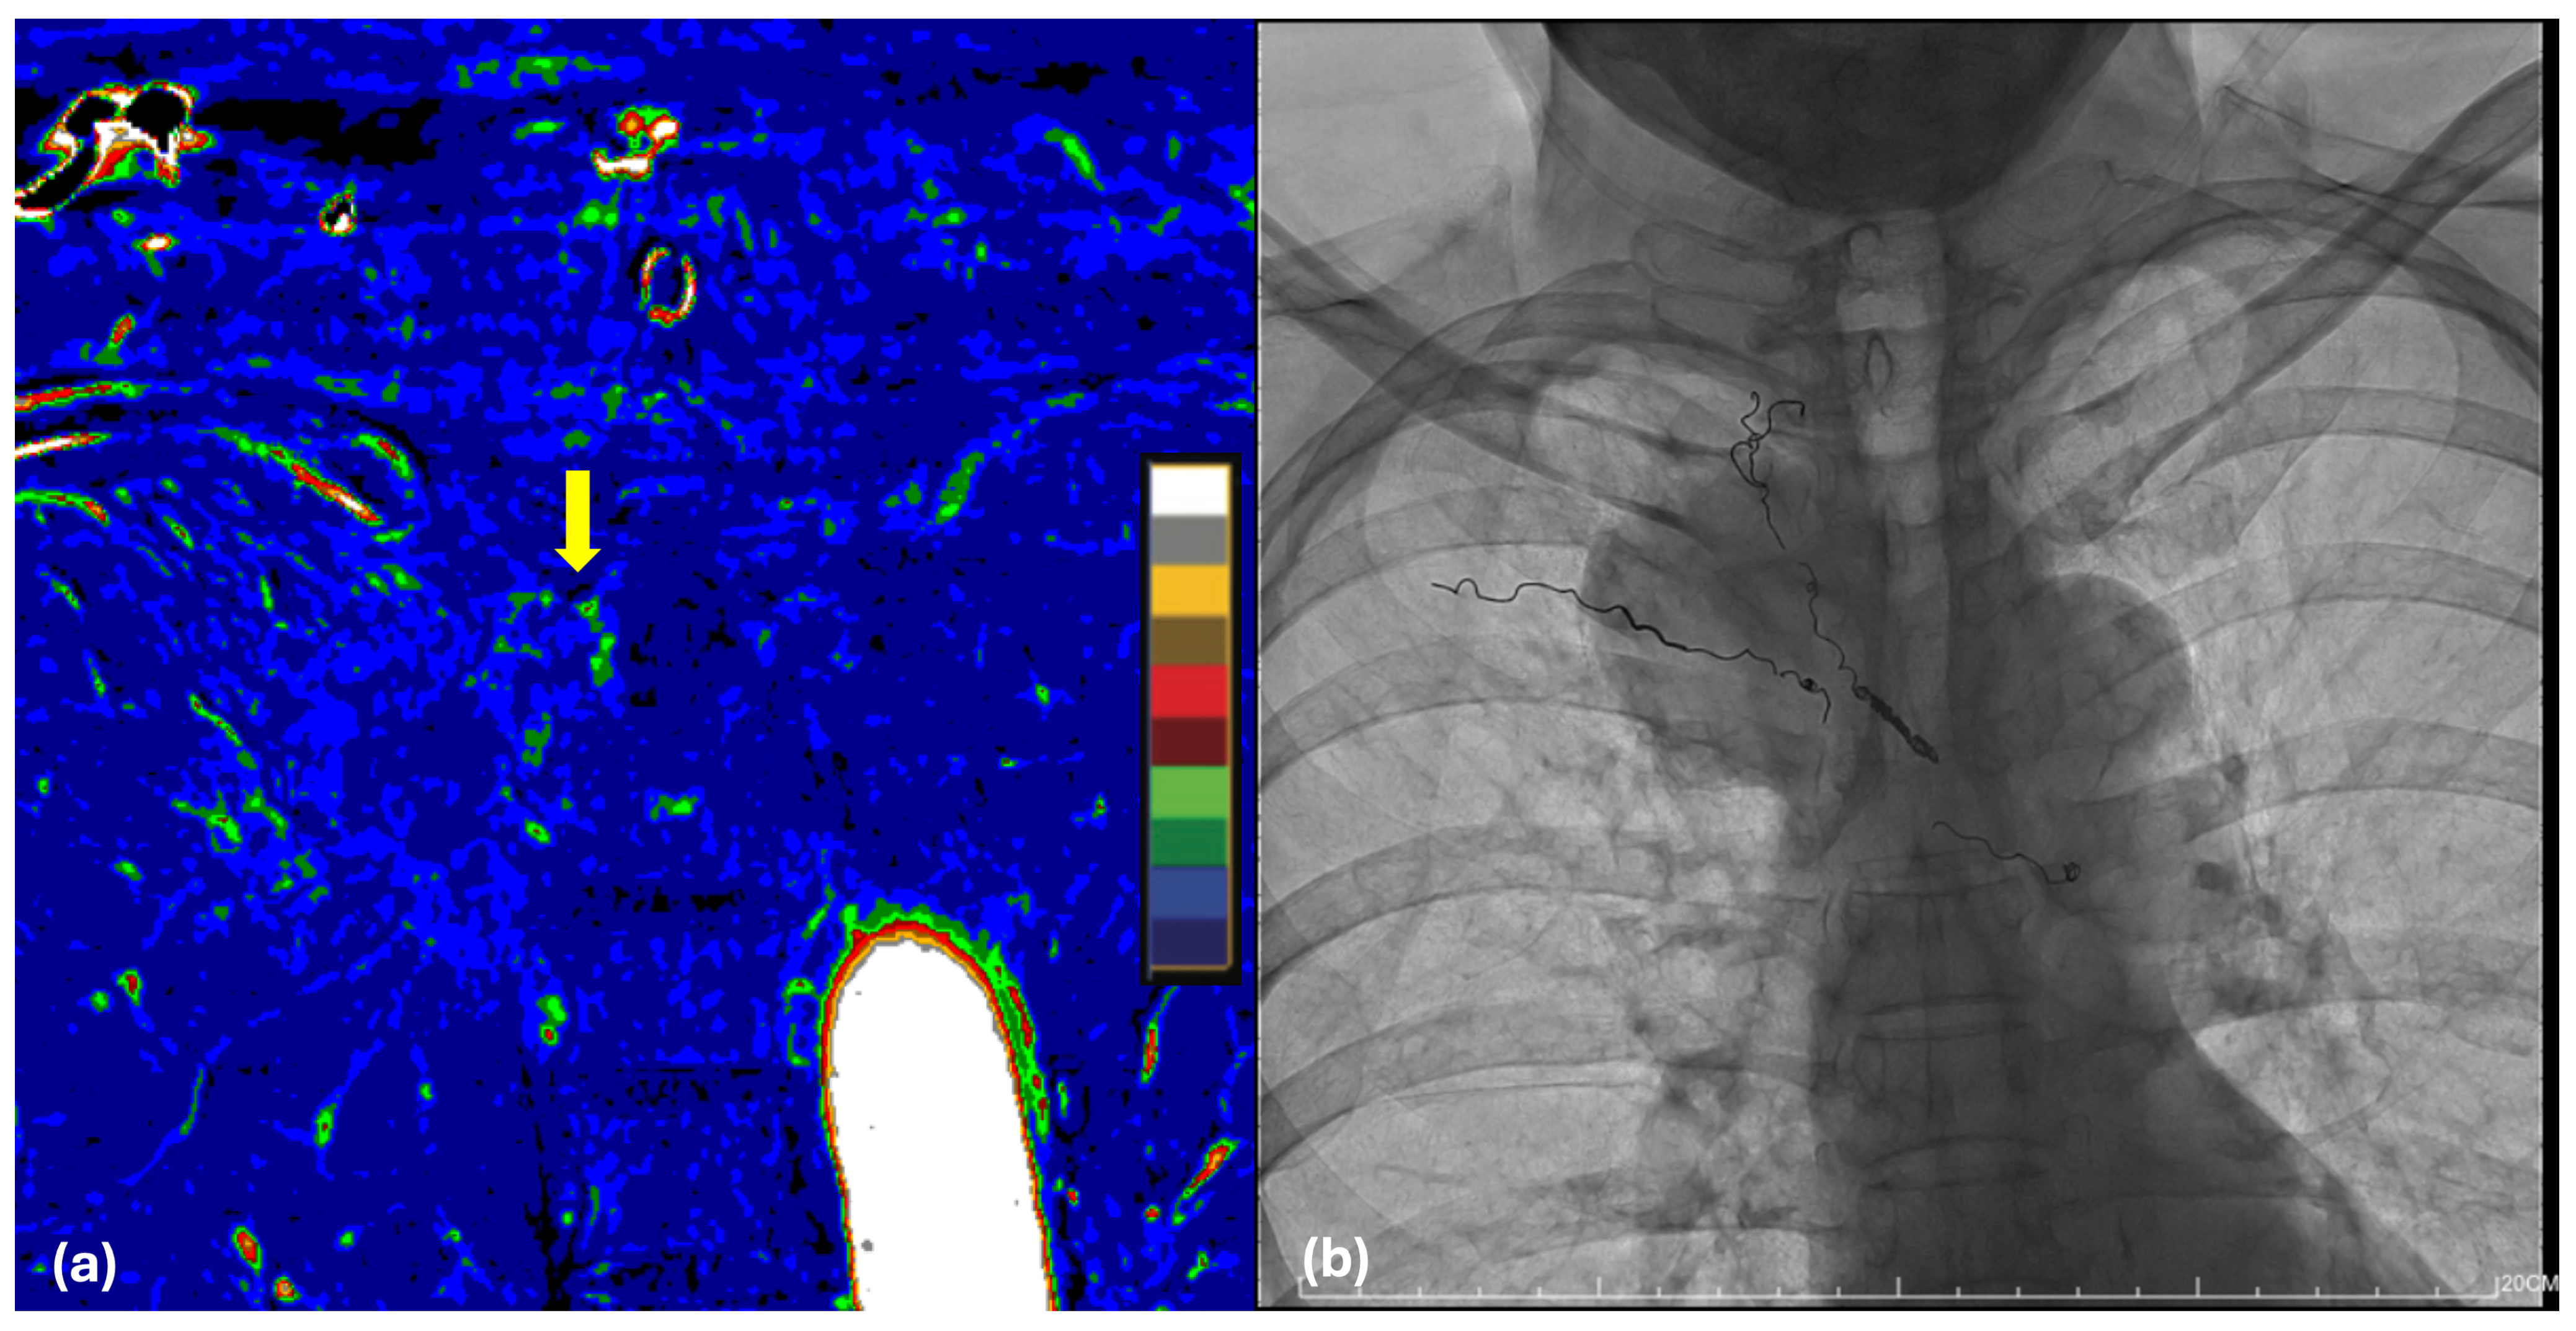

3.4. Surgical Access: Combined vs. Single-Stage Posterior

4.4. Hemostatic Optimization via Preoperative DECT and TAE

4.5. Surgical Efficiency and Hemostasis: Operative Duration and Blood Loss